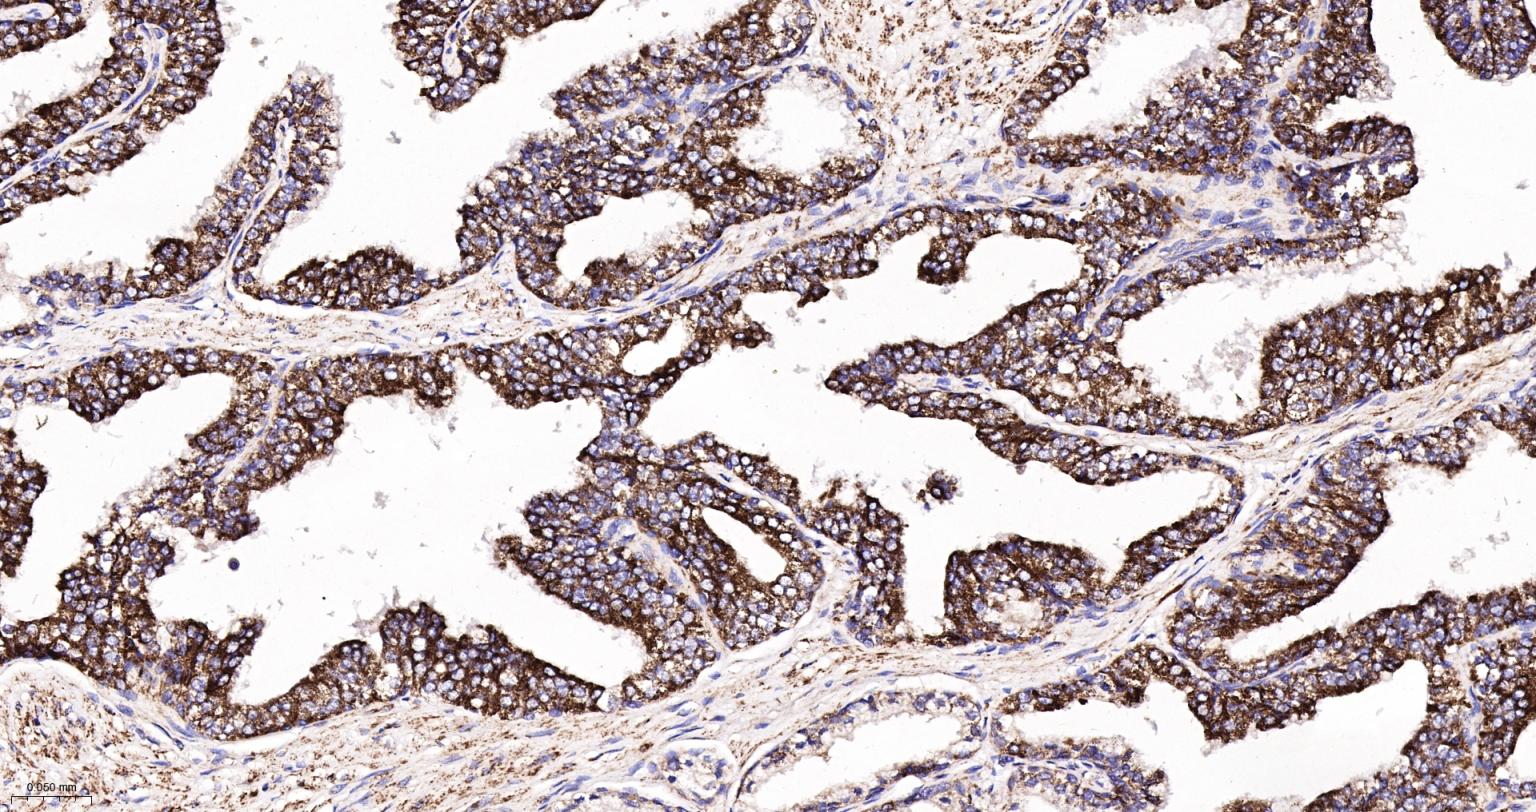

Paraformaldehyde-fixed, paraffin embedded Human Breast Cancer; Antigen retrieval by boiling in sodium citrate buffer (pH6.0) for 15 min; The section was incubated with IDH2 Monoclonal Antibody, Unconjugated (bsm-61585R) at 1:200 overnight at 4°C, followed by conjugation to the bs-0295G-HRP and DAB (C-0010) staining.